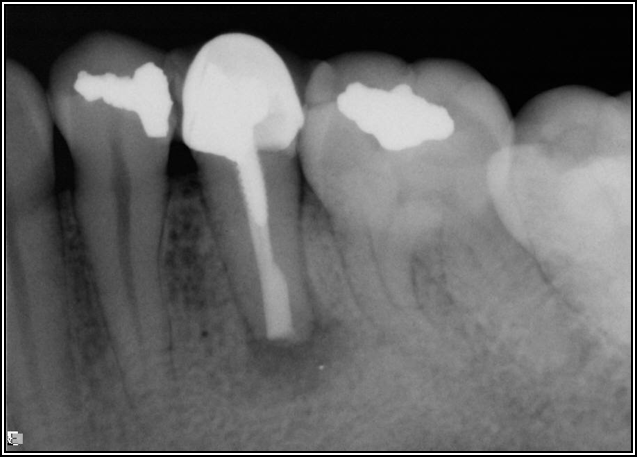

If a tooth stands alone, greater forces will be placed on it because it has no adjacent teeth to provide support. This situation will affect the decision-making process for placing a post. Figure 3 shows a tooth that was on an island and would be having three implants placed in front of it. The tooth would take a much greater beating than another tooth that had support proximally. Even though it had a good root canal, the clinician would need to account for whether the tooth would last until the implants integrated. Figure 4 shows a case that would quickly proceed to implants. The patient had a less-than-ideal bridge for over a decade, with decent endodontics and functionality. There was also an overhang on the premolar. The post was not ideal in this case because there was one distal canal and not all the gutta-percha was removed from it. An intimate fit should be the goal with the post and the walls. Whether using a threaded or non-threaded post, there should not be excess gutta-percha because it is not as solid as the tooth and will lead to greater movement. That movement on the tooth and bridge will create too much force and result in demise.

Fig 4. Case that quickly would proceed to implants.

Figure 4